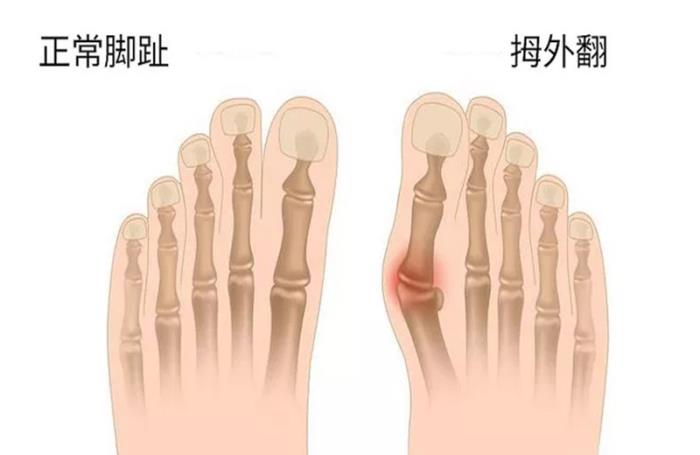

脚趾大骨在现代很多女性中最较为常见,不仅会影响到我们的美观,也会让我们觉得走路都会是一种痛苦。拇(踇)外翻又称“大脚骨”,外观上是拇趾在第一跖趾关节处向外侧偏斜移位压迫第二脚趾,并且在拇趾内侧出现骨性突起。病程较久的,在前脚掌能看到硬茧。造成拇指外翻的原因你了解多少呢?今天这篇文章我们一起来聊聊大脚趾的那些事儿。

大脚骨的主要表现为脚趾外翻、重叠、拇指关节会突出等,其主要原因就是长时间的站立、长期穿不合适的鞋子、穿尖头的高跟鞋。另有研究表明,拇外翻与遗传也有一定的关系,尤其是在青少年阶段,另外足趾的发育畸形,内翻成角,也是拇外翻 的一个重要因素,另外可能与一些疾病也有密切关系,比如类风湿性关节炎、扁平足等等也会引起。除此之外有些人为了美观不愿意穿凉鞋,这样长期的摩擦也会很容易出现一些脚类疾病,加重拇外翻的情况,前足变宽 ,横弓塌陷,由此运动能力也会受到影响,所以我们在发现这种情况的时候一定要尽早采取治疗措施。

拇指外翻可分为四个阶段: